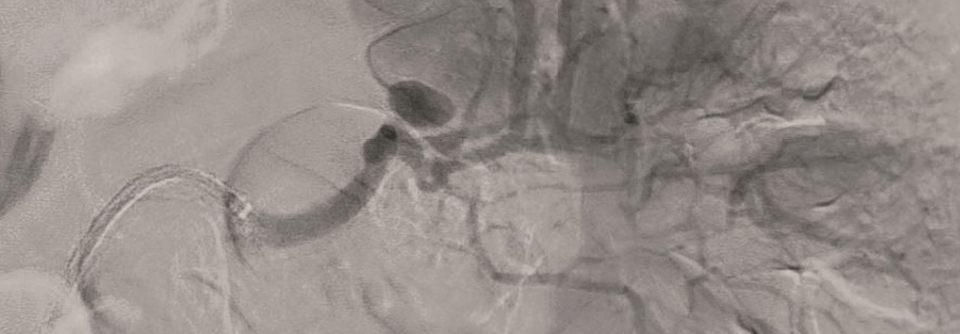

Hier haben die Gefäßverschlüsse zu zwei kleinen lakunären Infarkten geführt. Hier haben die Gefäßverschlüsse zu zwei kleinen lakunären Infarkten geführt. © wikimedia/Prashanthsaddala; Firat – stock.adobe.com